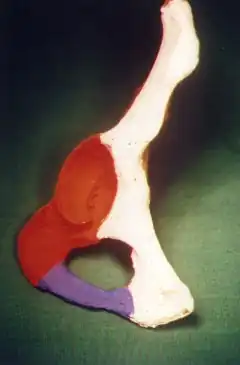

T shape fracture shown on bone model

T shape fracture shown on bone model -